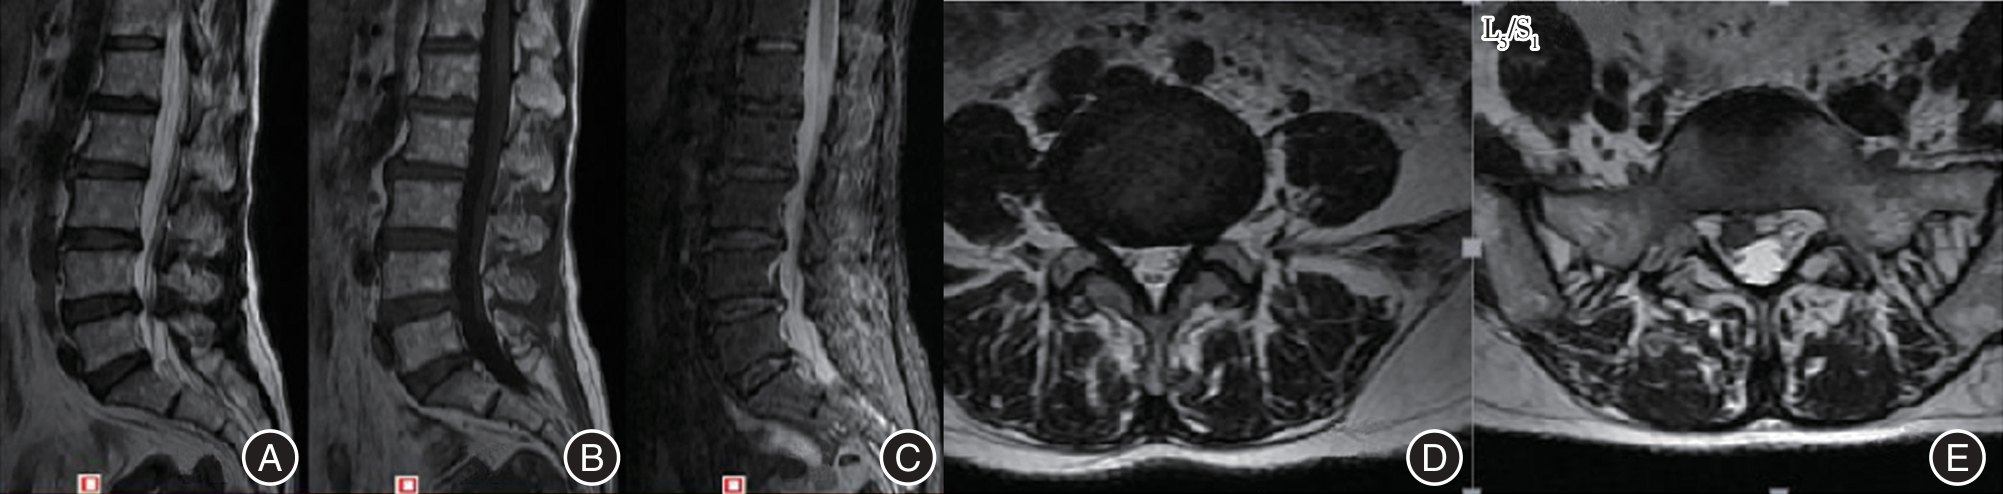

目的 探讨单一切口椎间孔镜治疗双节段腰椎管狭窄并腰椎间盘突出症的临床疗效。 方法 回顾性分析2016年3月至2018年5月在广西中医药大学第一附属医院脊柱骨伤科就诊的40例双节段腰椎管狭窄并腰椎间盘突出症患者临床资料,其中通过单一切口同时穿刺椎间孔镜治疗的患者11例(A组),通过单一切口前后穿刺椎间孔镜治疗的患者13例(B组),通过双切口前后穿刺椎间孔镜治疗的患者16例(C组)。记录患者的一般临床资料,三组不同时间点(术前、术后即刻、术后1周、术后1个月、末期随访)的VAS评分、JOA评分及临床疗效,并运用统计学进行分析。 结果 三组间手术时间、术中透视次数、皮肤切开长度和满意度差异均有统计学意义(P < 0.05);手术时间与手术方式在VAS、JOA评分上存在交互作用;手术时间、手术方式在VAS、JOA评分上存在主效应(P < 0.05);三组术后即刻、术后1周、术后1个月、末期随访与术前在VAS、JOA评分上比较差异均有统计学意义(P < 0.05);三组间术后即刻在VAS、JOA评分上差异有统计学意义(P < 0.05);三组间术后1周在VAS评分上差异有统计意义(P < 0.05)。 结论 单一切口椎间孔镜技术同时减压双节段腰椎管狭窄并腰椎间盘突出症的有效手段,具有手术时间短、术中透视少,损伤小等优势,患者满意,值得临床推广应用。

Objective To evaluate the clinical effectiveness of single?incision intervertebral foraminotomy in treating double?segment lumbar spinal stenosis accompanied by lumbar disc herniation. Methods A retrospective analysis was conducted on 40 cases of double?segment lumbar spinal stenosis and lumbar disc herniation treated in our orthopedic (spinal surgery) department from March 2016 to May 2018. Among these cases, 11 patients (Group A) were treated with percutaneous discectomy, 13 patients (Group B) underwent percutaneous endoscopic discectomy, and 16 patients (Group C) received double?incision percutaneous surgery. General clinical data for all patients were recorded. Visual Analog Scale (VAS) scores, Japanese Orthopaedic Association (JOA) scores, and clinical outcomes were assessed at five different time points: preoperatively, immediately postoperatively, one week postoperatively, one month postoperatively, and at the final follow?up. Statistical analysis was performed on the collected data. Results The operation time, the number of fluoroscopies performed on the hands, the length of the skin incision, and patient satisfaction were all statistically significant (P < 0.05). An interaction effect was observed between the operation time and the surgical procedure on both the VAS and JOA scores. Both the operation time and the surgical method had significant main effects on the VAS and JOA scores (P < 0.05). Significant differences in VAS and JOA scores were found among the three groups immediately post?surgery, one week post?surgery, one month post?operation, and at the end of the study (P < 0.05). Immediately after surgery, there were statistically significant differences in VAS and JOA scores among the three groups (P < 0.05). One week post?surgery, there were also statistically significant differences in VAS scores among the three groups (P < 0.05). Conclusions The single?incision intervertebral foramen technique is an effective approach for simultaneously addressing double?segment lumbar spinal stenosis and lumbar disc herniation through decompression. This method boasts a shorter operative duration, reduced intraoperative radiation exposure, and minimal tissue damage. Patient satisfaction is high, making it a valuable addition to clinical practice.